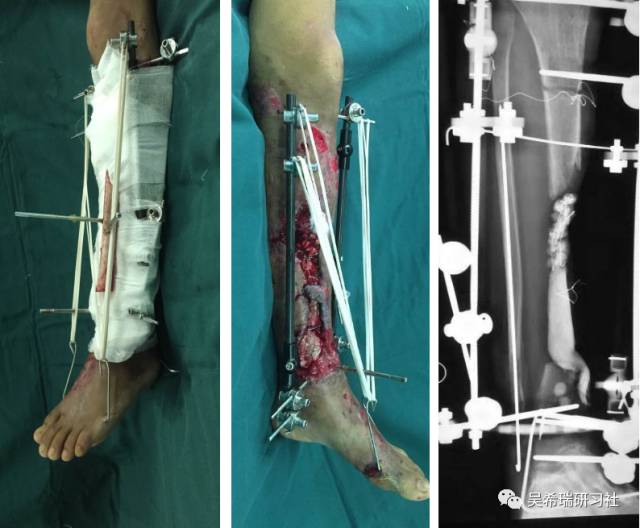

车祸伤多发伤胫骨近端开放骨折软组织缺损右上肢截肢

TIPS:开放骨折外固定游离植皮缩小伤口搬移+半开放植骨半开放植骨=骨水泥技术+开放植骨+骨搬移横向、前后调整搬移骨块下地走路刺激骨愈合早期关节功能锻炼